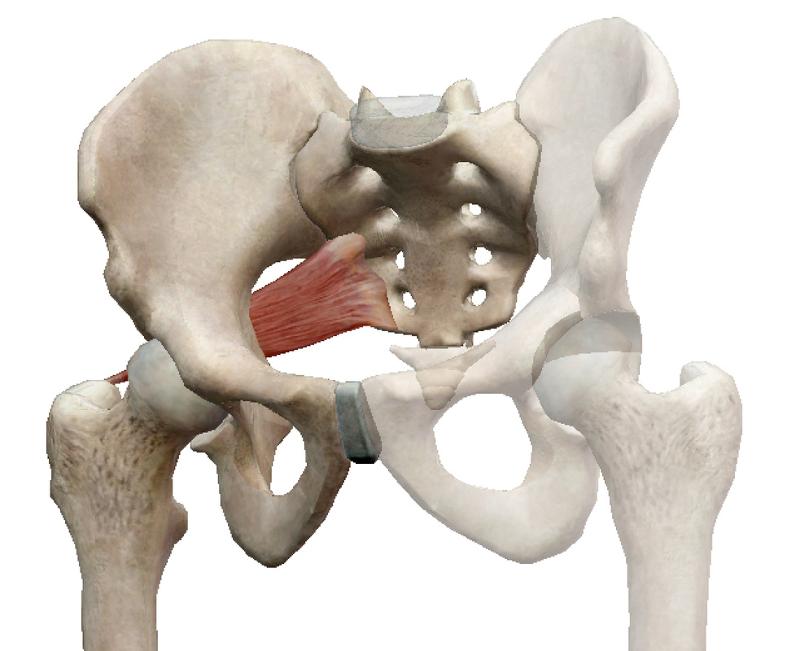

Анатомия мышц: Пириформис